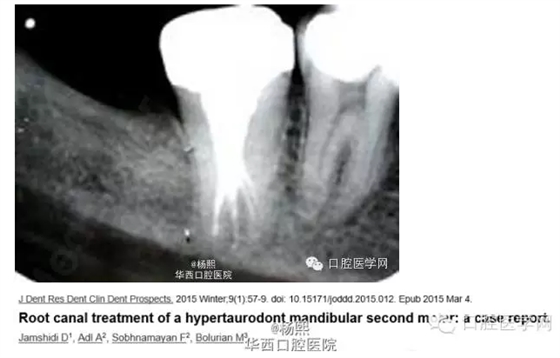

這個病例挺有意思的,分享給大家。病例為JamshidiD,Adl,Sobhnamayan,F(xiàn),Bolurian M.J Dent ResDent Clin Dent Prospects.2015 Winter;9(1):57-9.doi:10.15171/joddd.2015.012.Epub 2015Mar4.

隨訪:18月后隨訪X線片示根尖周暗影消失。

討論:此病例屬于牙發(fā)育異常中的牛牙癥,為重度牛牙癥。牛牙癥(Taurodontism)是指牙髓頂至髓底的高度高于正常,而釉質(zhì)牙骨質(zhì)界的水平?jīng)]有改變、造成髓室向根尖延伸超過牙頸部,根分叉靠近根尖,牛牙癥 根據(jù)髓底向根尖方向位移的程度分為輕度、中度和重度。